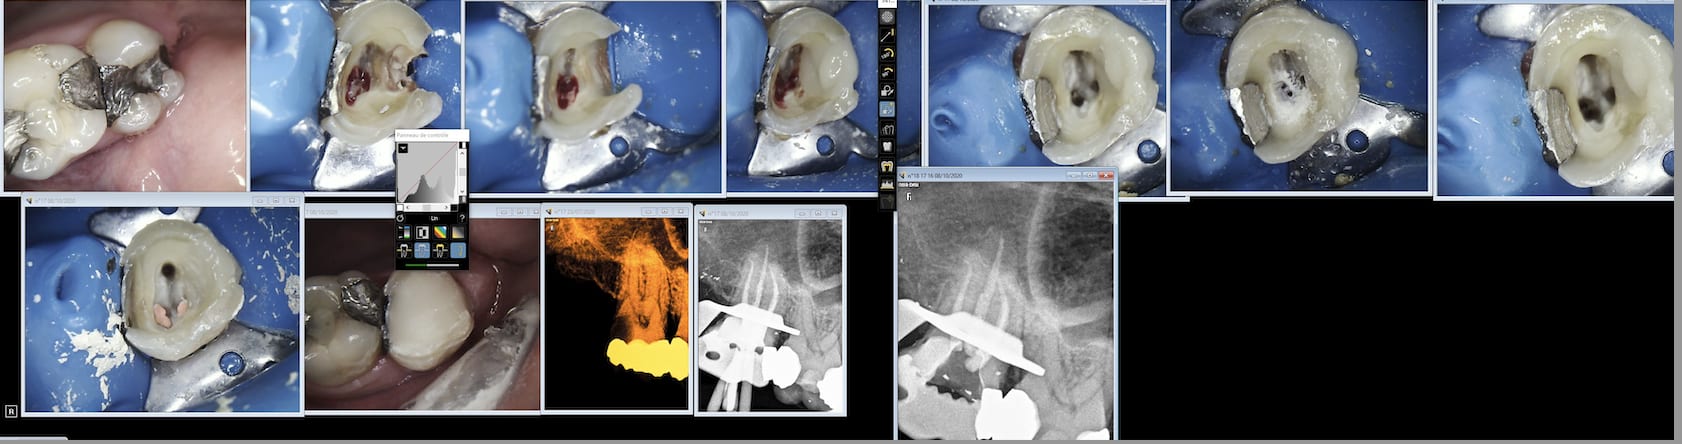

Mais binbin il a pas pris des photos de ses assainissements parodontaux fictifs. Tu factures tu en apportes la preuve . point . binbin.

Le motif était les douleurs secteur 1. La dent causale est pour moi la 17 avec importante lipoe et douleurs à la percussion.

Les 13 et 15 étaient, d’après le devis, nécrosées. Il y a eu des rcpe devisées pour les deux dents puis des reconstructions de moignons sans ancrage.

Ras en 13 et 15 si ce n’est la reprise de carie. Je ne suis pas certain que les couronnes aient été faites par cet endo mais je revois le patient pour sa 12 et lui demanderai.

Et si t'avais l'habitude d'en faire tu t'apercevrais que c'est pas si facile que ça à matricer en sous gingival.

C'est con parceque quand tu fais pas de RCPE tu peux quand même les facturer les photos avec tact et mesure. -)

Je sais bien que le ridicule ne tue pas, mais de là à facturer des photos faut pas pousser, déjà que je ne facture pas les rcpe…